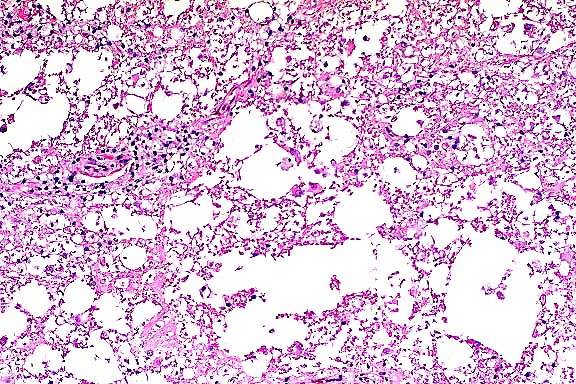

- The giant cell pneumonia seen in this case is typical of

SIVmac-induced giant cell pneumonia and is characterized by extensive

infiltration of alveolar septa and spaces by numerous macrophages

with abundant foamy cytoplasm and multinucleate giant cells of

macrophage-monocyte origin. The interstitial pneumonia with karyomegaly

and intranuclear inclusions is characteristic of cytomegalovirus,

a common secondary infection in SIVmac-infected animals. On transmission

electron microscopy, an unidentified cell in the lung was found

to contain an intranuclear inclusion body with peripheral clearing

of the nuclear chromatin. Dispersing the nuclear chromatin were

viral particles measuring 100 to 110 nm. The viral particle size

and morphology were consistent with those of the herpesviridae

group.

- Case 22-1. Lung. A syncytial giant cell is accompanied

by abundant foamy alveolar macrophages within and thickening

the septal walls (interstitial pneumonia).

- Conference Note: Variably affecting the sections of

lung, there are multifocal to coalescing areas of atelectasis

and consolidation. Bronchioles are partially or completely filled

by numerous viable and degenerate neutrophils admixed with fewer

macrophages, necrotic respiratory epithelial cells, abundant

cellular debris, few bacilli, and mucin. There is occasional

segmental attenuation and loss of the bronchiolar epithelium.

Similar inflammatory cells partially or completely fill adjacent

alveoli.

- Additionally, there is multifocal thickening of alveolar

septa by neutrophils, macrophages, and type II pneumocytes. Pneumocytes

sometimes contain eosinophilic intranuclear inclusions that marginate

the chromatin, or large, basophilic inclusions that completely

fill the enlarged the nuclei. Alveoli sometimes contain large

multinucleate cells with abundant eosinophilic cytoplasm and

up to 15 peripheral nuclei. In addition, there are fewer multinucleate

cells with less cytoplasm and fewer, centrally located, nuclei.

The interstitial changes and multinucleate cells are most readily

observed at the interface of less affected lung parenchyma and

areas of consolidation.